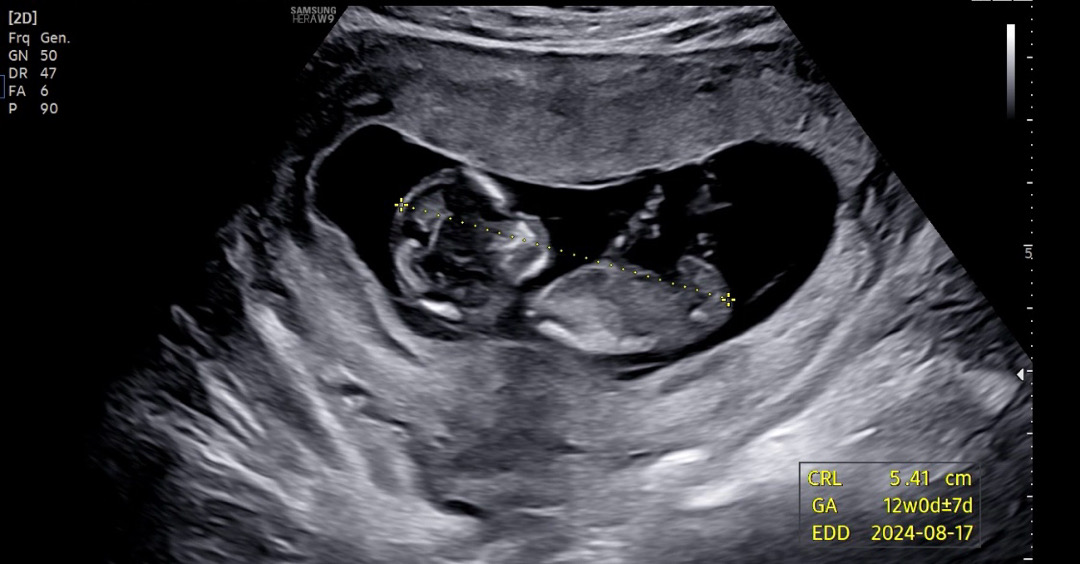

12주 초음파 각도법

각도법으로 보일까요!? 도와주세요!

아기 머리봐요 너무 귀여워요!!